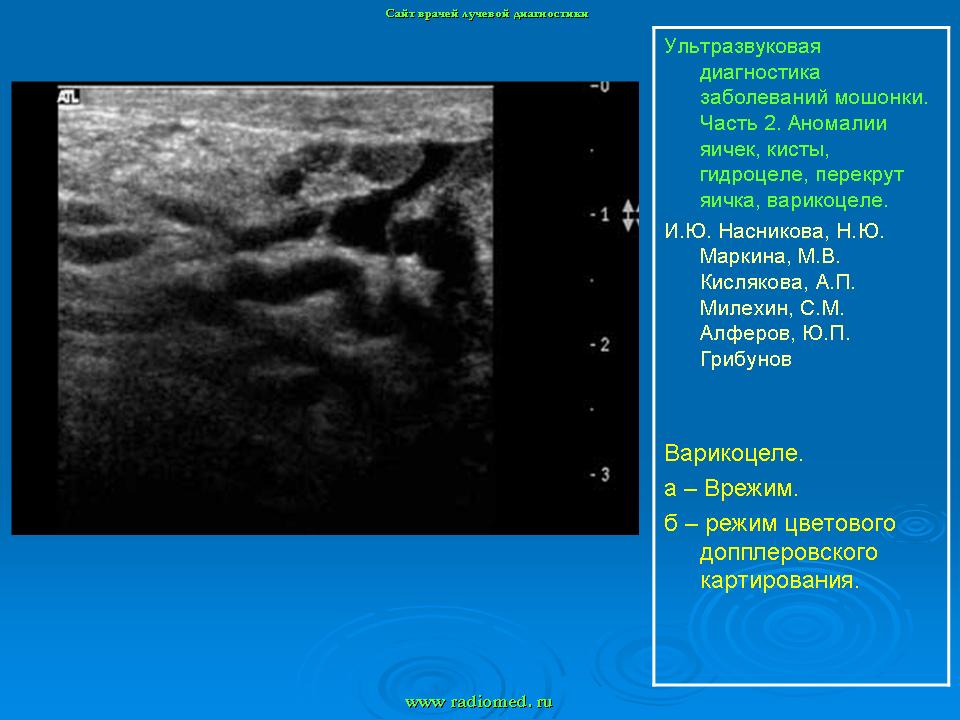

УЗИ. УЗ - диагностика заболеваний мошонки. +

УЗ - диагностика заболеваний мошонки.